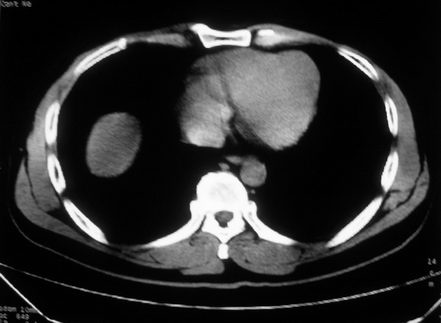

男,体查发现右肝低密度,右肾高密度结节影。高密度ct值92hu,囊肿?

肝右叶囊肿或血管瘤?右肾高密度囊肿。建议增强。

肝右叶圆形低密度灶,考虑囊肿或血管瘤,建议ct增强检查;右肾包膜下高密度圆形灶,考虑:囊肿并出血